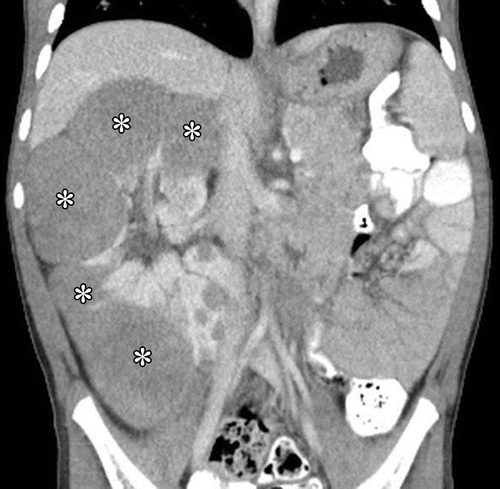

Associate dwith DICER 1 mutation and herniates to renal pelvis

MULTILOCULAR CYSTIC NEPHROMA (Dicer 1 MUTATION: pleuropulmonary blastoma)

Herniates to the renal pelvis

No solid component or necrosis.

Michael Jackson tumor (boys and young girls)

4 year old.